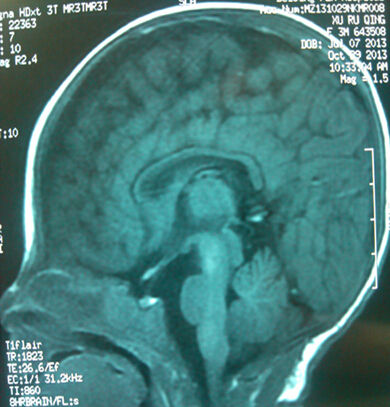

这是一位男孩,37周,于2012.5.23剖宫产,出生体重2700克,出生时无窒息,生后4天来就诊。头颅MRI显示颅内出血Ⅲ°,胼胝体缺如。开始指导早期干预。3个月29天视听反应好,头竖立时晃动,余神经运动检查未见异常。10.5月视听反应好,头竖立时晃动,余神经运动检查未见异常,智测DQ84.5。1.5岁时,独走自如,能说单词,神经运动检查未见异常,智测DQ96.3。

胼胝体是大脑左右半球联系的神经纤维组成的大脑重要结构。上面报告的病孩出生时胼胝体缺如。但是,他到1.5岁时运动和智力完全正常。大脑就有这么神奇的代偿能力。